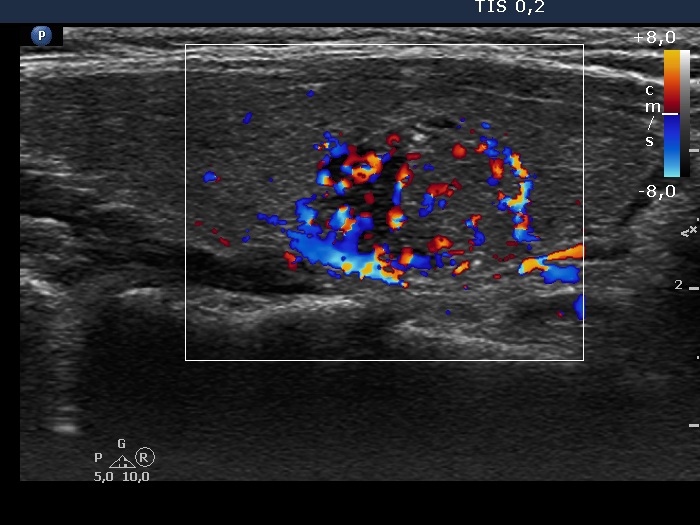

100 consecutive cases of papillary cancer - case 078 (ultrasonographic picture 6)

Right lobe, longitudinal scan, color Doppler mode.